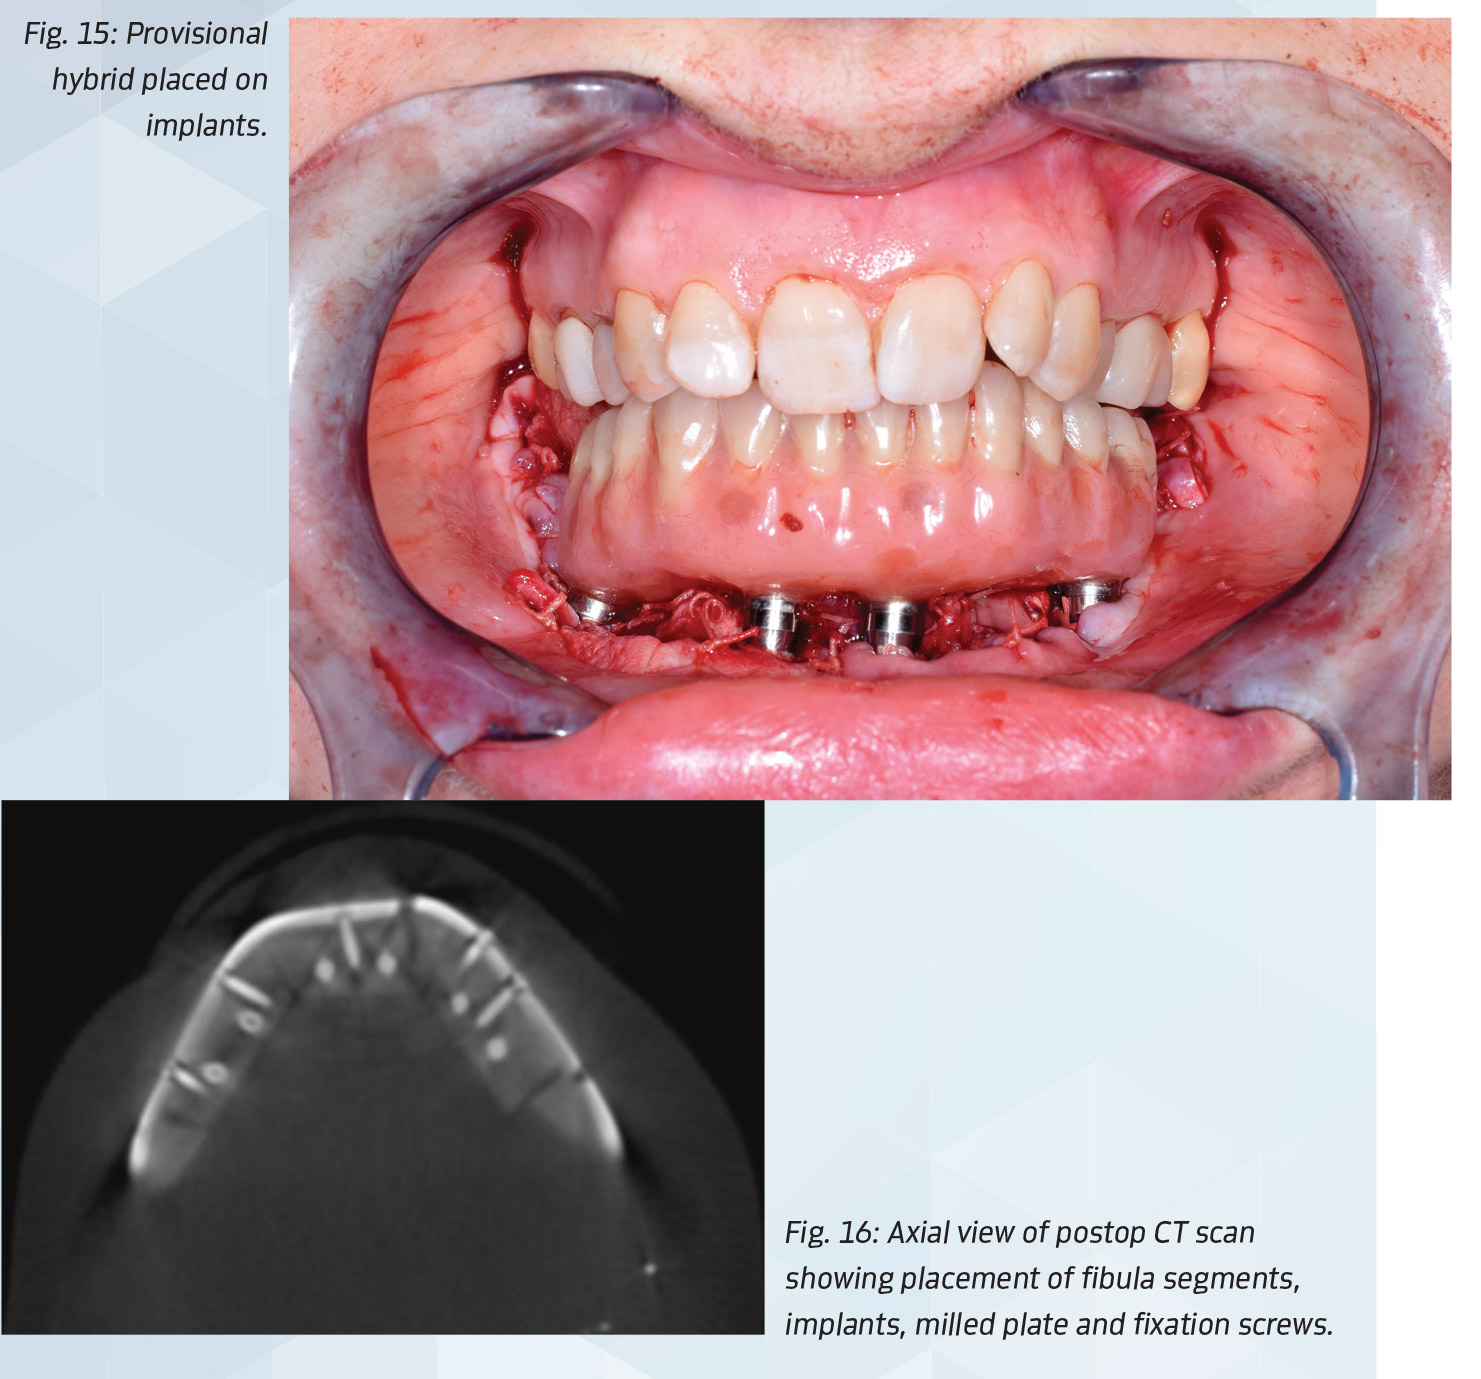

The neck was closed with 3-0 vicryl at the level of the platysma muscle, and 4-0 Prolene for skin. The oral mucosa was sutured to the fibula, with care to maintain exposure of the abutments (Fig. 14). The final hybrid prosthesis was placed and occlusion verified (Fig. 15). A postoperative CBCT scan showed the accuracy of implant placement, fixation screw placement and bone positioning possible with virtual 3-D planning (Figs. 16 and 17).